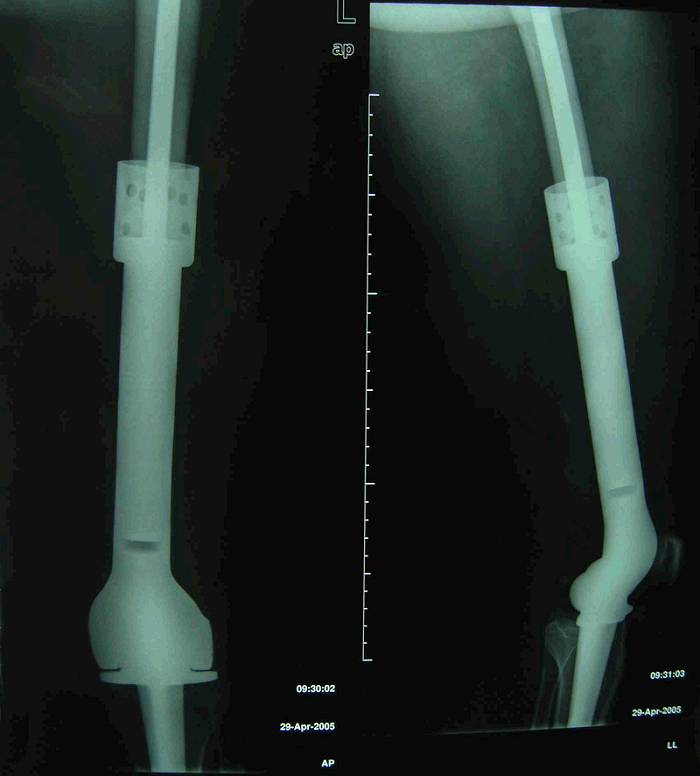

图 17 术后X线片